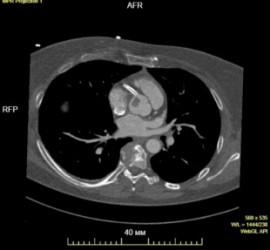

«Выполнив дополнительные обследования, мы нашли истинную причину приступов. Оказалось, у пациентки была папиллярная фиброэластома (достаточно редкая форма доброкачественной опухоли сердца). Она очень часто долго протекает бессимптомно, поскольку ее размер не превышает 1,5–2 см. Проявиться она может в виде нарушения мозгового кровообращения, когда или фрагменты самой опухоли, или тромботические массы отрываются и с током крови попадают в сосуды головного мозга. У нашей пациентки случилось по-другому — фиброэластома вызвала инфаркт миокарда», — вспоминает заведующий отделением сердечно-сосудистой хирургии № 1 Центра Алмазова Александр Станиславович Гневашев.

Наиболее часто папиллярная фиброэластома крепится к аортальному клапану или к стенкам аорты на тонкой ножке, а с током крови может временно заноситься в устье коронарной артерии, прекращая кровоток по ней. При этом у больного возникают боли в груди, очень типичные для стенокардии, позже, когда опухоль покидает устье, симптомы проходят. Исследования, выполненные новгородскими врачами, несколько раз не показывали стенокардию или инфаркт именно потому, что в этот момент опухоль перемещалась и открывала кровоток.

К счастью, несмотря на перенесенный инфаркт и стентирование, у женщины сохранена сократительная способность миокарда. Сразу после поступления в Центр Алмазова, в день госпитализации ей была выполнена кардиохирургическая операция, в ходе которой папиллярная фиброэластома удалена.